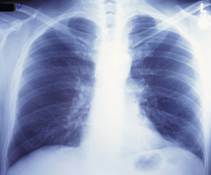

الاشعة السينية فوائدها واضرارها

الاشعة السينية فوائدها واضرارها موسوعة

بحث عن الأشعة السينية ما بين الفوائد والأضرار موسوعة

فوائد واضرار الاشعه السينية للحامل والأطفال وكبار السن

ما هي الاشعة السينية وفوائدها واضرارها موسوعة دار الطب

الاشعة السينية مخاطرها وفوائدها وطرق استخدامها مستشفيات مغربي

الأشعة السينية استخدامات وفوائد الأشعة أضرارها المحتملة وطريقة عملها

فوائد واضرار الاشعة السينية على جسم الانسان وطرق استخدامها